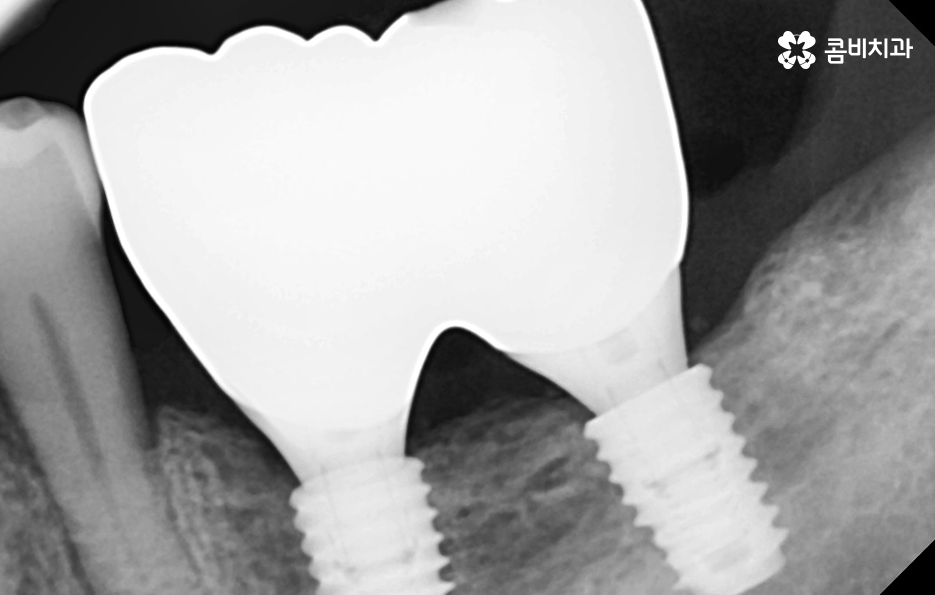

임플란트의 시술 원리는 잇몸 뼈에 식립하게 되기 때문에 충분한 골조직이 없을 때는 시술 성공률도 낮아질 뿐 아니라 장기적인 안정성도 떨어지기 때문에 잇몸 뼈가 부족하신 분들은 뼈이식을 추가적으로 해야할 수 있어요

만약 치주염으로 인해 50대임플란트 해야 하는 분들의 경우에는 뼈이식을 추가적으로 받아야 하는 경우가 있겠고 임플란트의 안정성을 확보하기 위해서는 임플란트를 고정해줄 수 있는 일정한 두께와 식립 깊이, 골질이 건강해야 하는데요

또한 뼈이식을 해야 하더라도 잇몸을 되도록 보존하는 치료를 하고 치료 시점을 의사와 잘 상의한다면 뼈이식의 양을 줄일 수 있고 회복기간도 상대적으로 줄일 수 있다는 점에서 임플란트 치료 원리를 먼저 이해하시고 대처하시길 바라고 있어요